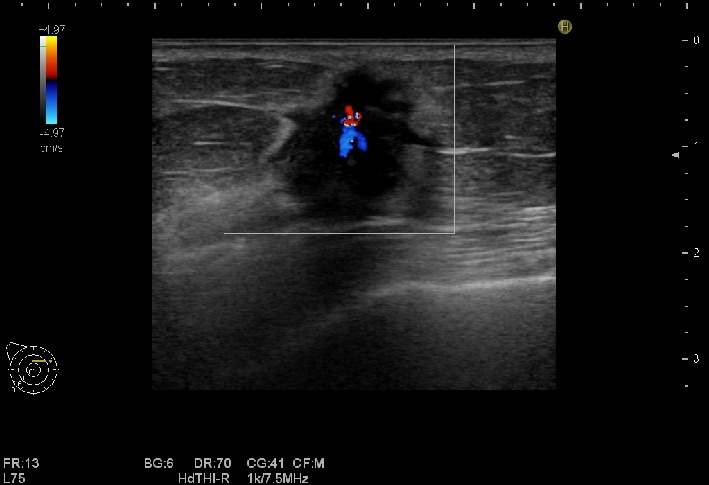

乳腺超音波検査

乳腺内の腫瘤や、乳腺構造の変化などを観察します。腋窩のリンパ節もチェックします。乳腺検査は女性技師が担当します。

必要に応じて、外科のドクターによる超音波ガイド下針生検を行っています。

血流をみるカラードプラ